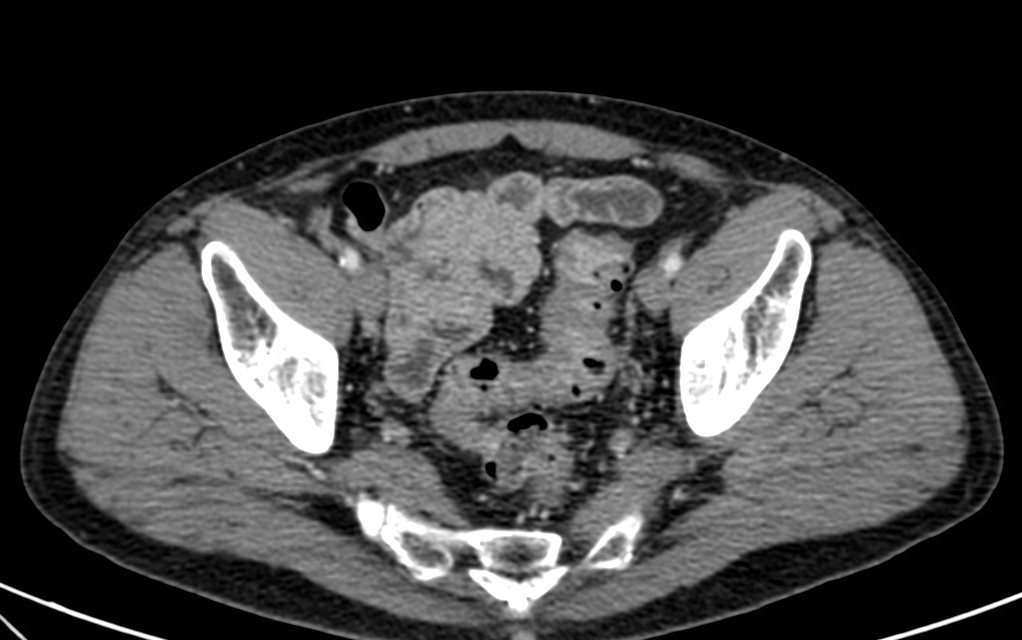

TC ABDOMEN: Se confirman los hallazgos vistos en ecografía. Se aprecia un engrosamiento mural > 4mm de un segmento aproximado de 5.5 cm de longitud con infiltración de la grasa adyacente y sin visualizar colecciones ni gas extraluminal, hallazgos compatibles con diverticulitis aguda no complicada.

CONCLUSIÓN: Diverticulitis aguda no complicada. HINCHEY grado 0